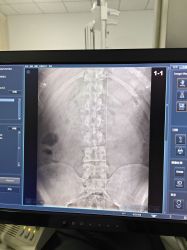

无标题 无名氏 2024-02-26(一)21:11:22 ID:kkljdb7 [举报] No.61410549 管理

>>No.61409941

片子来力

无标题 无名氏 2024-02-26(一)21:11:53 ID:kkljdb7 [举报] No.61410553 管理

还有一张

无标题 无名氏 2024-02-26(一)21:24:32 ID:SmS1n2r (PO主) [举报] No.61410671 管理

>>No.61410553

有点点明显了已经,平常会不会下背痛,腰背累,晨僵之类的

无标题 无名氏 2024-02-26(一)21:52:47 ID:kkljdb7 [举报] No.61410969 管理

>>No.61410671

没有什么感觉啊(|||゚Д゚)

无标题 无名氏 2024-02-26(一)21:53:18 ID:kkljdb7 [举报] No.61410977 管理

或者是我已经莫名其妙的适应了,现在察觉不到?

无标题 无名氏 2024-02-26(一)21:54:01 ID:SmS1n2r (PO主) [举报] No.61410983 管理

>>No.61410969

没感觉的话不管先,不过平常注意矫正姿势,坐正睡平,也千万不要去按摩店

无标题 无名氏 2024-02-26(一)21:57:21 ID:kkljdb7 [举报] No.61411021 管理

>>No.61410983

收到|∀゚,运动健身啥的需要注意什么嘛 先谢过po了

无标题 无名氏 2024-02-26(一)22:19:35 ID:SmS1n2r (PO主) [举报] No.61411206 管理

>>No.61411021

硬举先不做先,卧推什么的可以,深蹲这种也儘量少一点(`・ω・)